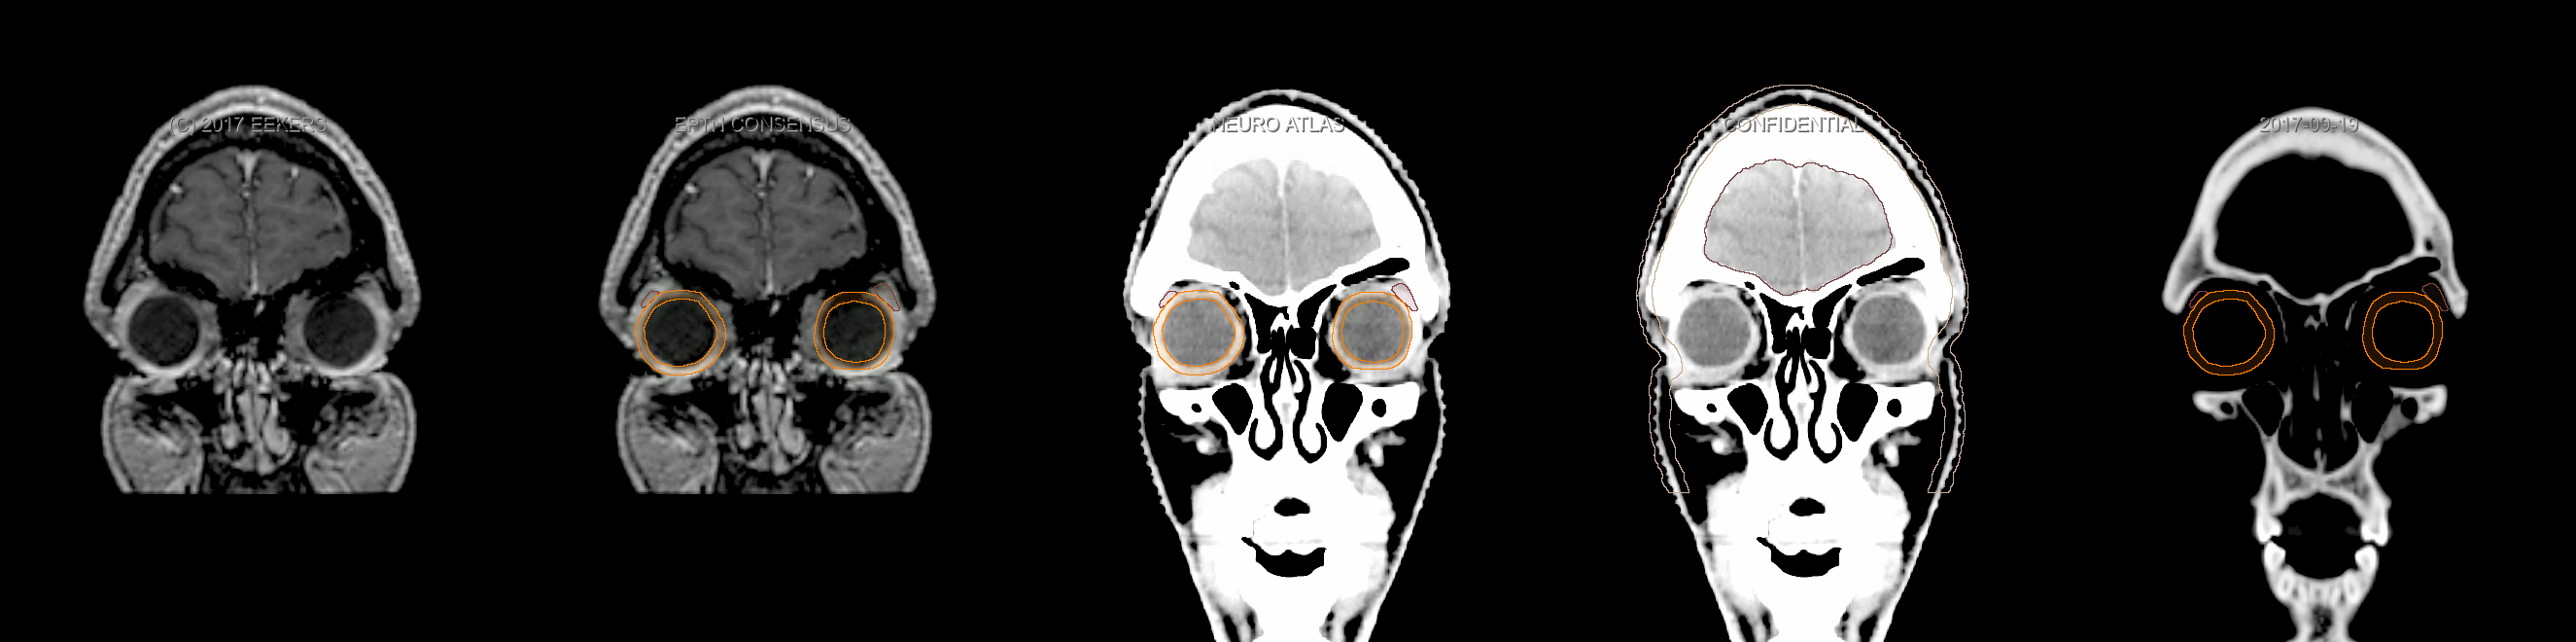

Three-dimensional delineation of the fifteen consensus OARs for neuro-oncology are shown on CT and 3 Tesla (3T) MR images (slice thickness 1 mm with intravenous contrast agent). All are presented in transversal, sagittal and coronal view.

From left to right: MR without structures, MR with structures, CT (WW/WL 120/40) with structures, CT (WW/WL 120/40) with Brain and Brainstem Surface, CT (WW/WL 1500/120)with structures